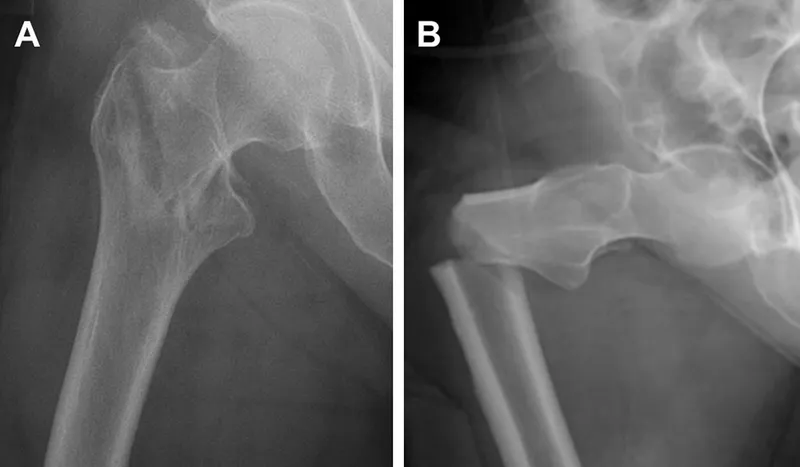

- Hip (femoral neck, intertrochanteric)

- X-ray: Confirms fracture.

- Hip: ORIF (screws, plates, nails), hemiarthroplasty, total hip replacement (THR).

⭐ Vertebral, hip (femoral neck, intertrochanteric), and distal radius (Colles') fractures are the most common sites for fragility fractures.